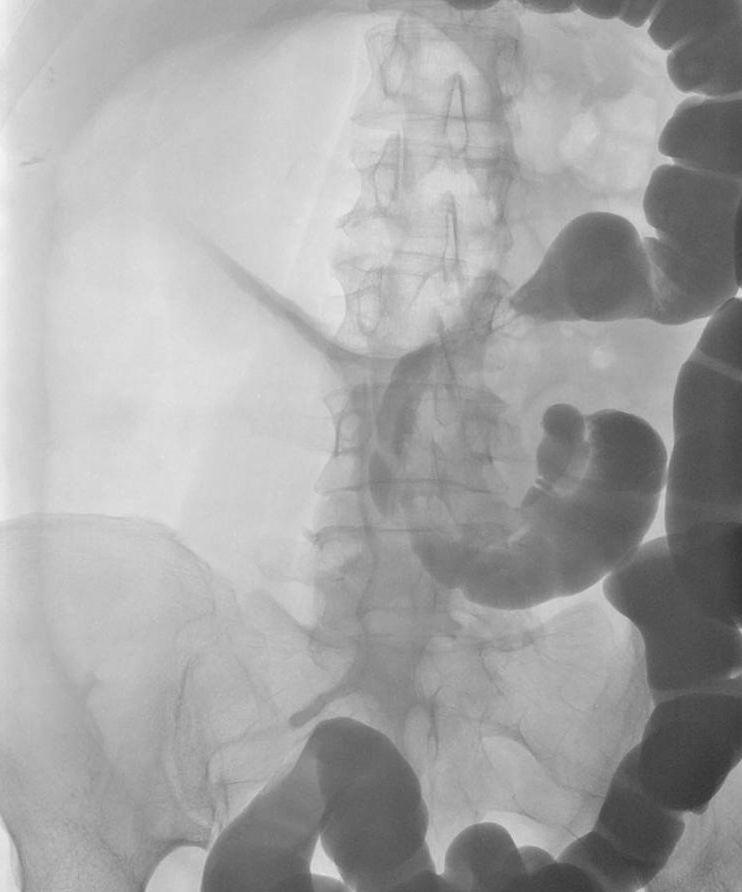

Een 48-jarige vrouw bezocht de Spoedeisende Hulp vanwege peracuut ontstane buikpijn. Zij had geen passagestoornissen en geen opgeblazen gevoel. Wel klaagde zij over misselijkheid. Bij lichamelijk onderzoek zagen wij een niet-zieke vrouw met een bolle buik, niet-afwijkende peristaltiek en drukpijn in epigastrio. Haar voorgeschiedenis vermeldde een navelbreukcorrectie als kind en 6 maanden geleden een strengileus.

Wat is uw diagnose?

Antwoord